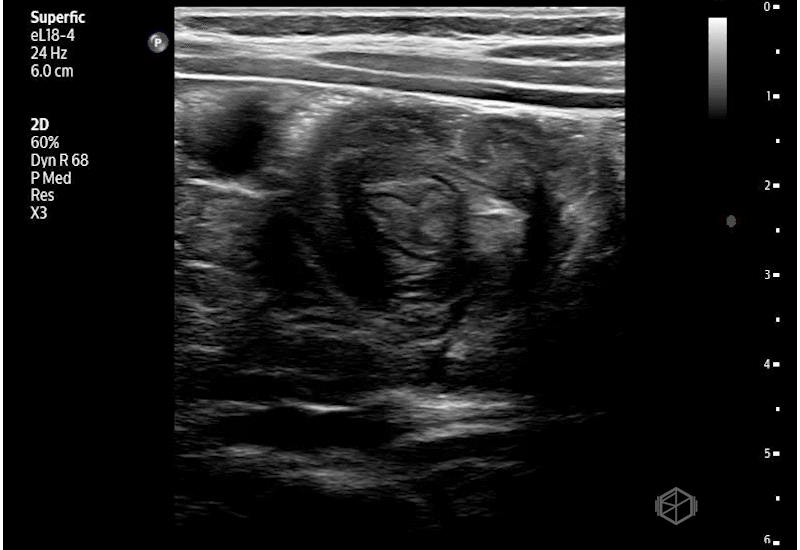

Bedside abdominal ultrasound revealed: A “target” (donut) like structure in the right upper quadrant on transverse view. Concentric hypoechoic and hyperechoic rings representing telescoped bowel. A “pseudokidney” sign on longitudinal view. Bowel-within-bowel configuration measuring >2cm in diameter. No obvious free fluid was noted.

Diagnosis: Ileo-colic intussusception

• The “target” (donut/bull’s-eye) sign on transverse view and the “pseudokidney” sign on longitudinal view are classic sonographic findings of ileocolic intussusception.

• A bowel mass measuring >2-3 cm in diameter supports ileocolic intussusception and helps distinguish it from transient small bowel–small bowel intussusception. A target sign with a diameter of ≤ 2cm suggests a small bowel intussusception, which generally self-resolve, and rarely require reduction (📚 PMID: 15467415).